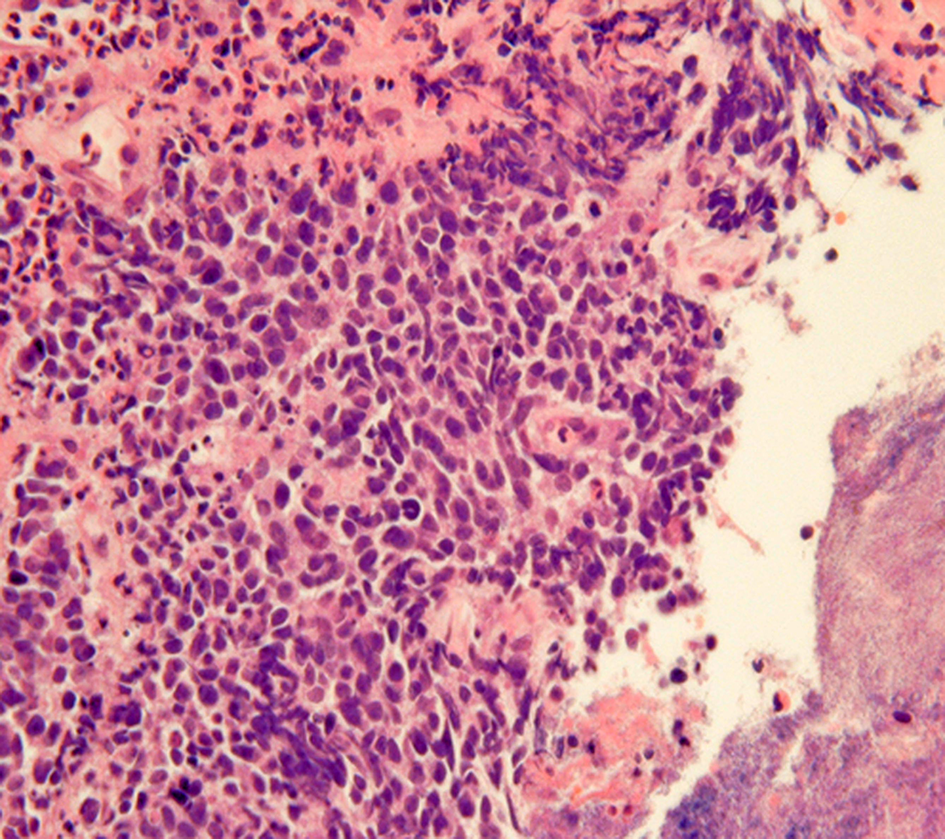

Obtaining GI-NEN tissues by endoscopic forceps biopsy is often difficult due to their location in the deep mucosa and submucosa. Even if biopsy is successful, the diagnosis of GI-NEN using biopsy material is sometimes difficult due to small specimen size or “crush” artifacts (Figure 3), which can lead to misdiagnosis (Hoda and Hajdu, 1992; Brenner et al., 2004). Nevertheless, accurate diagnosis from the initial biopsy is important because therapy could differ depending on the diagnosis. Therefore, analysis using neuroendocrine markers should be performed to rule out NENs when tumors have strong crush artifacts in biopsy materials. Fine-needle aspiration cytology is useful for diagnosing GI-NENs because they are generally located in deep areas of the gastrointestinal tract (Benya et al., 1993; Acs et al., 2000; Tasso et al., 2012). Brushing cytology for esophageal small-cell carcinoma also has been reported (Chen, 2000).

Figure 3

“Crush”artifacts of esophageal small cell carcinoma (upper right) [hematoxylinand eosin (H and E) stain].